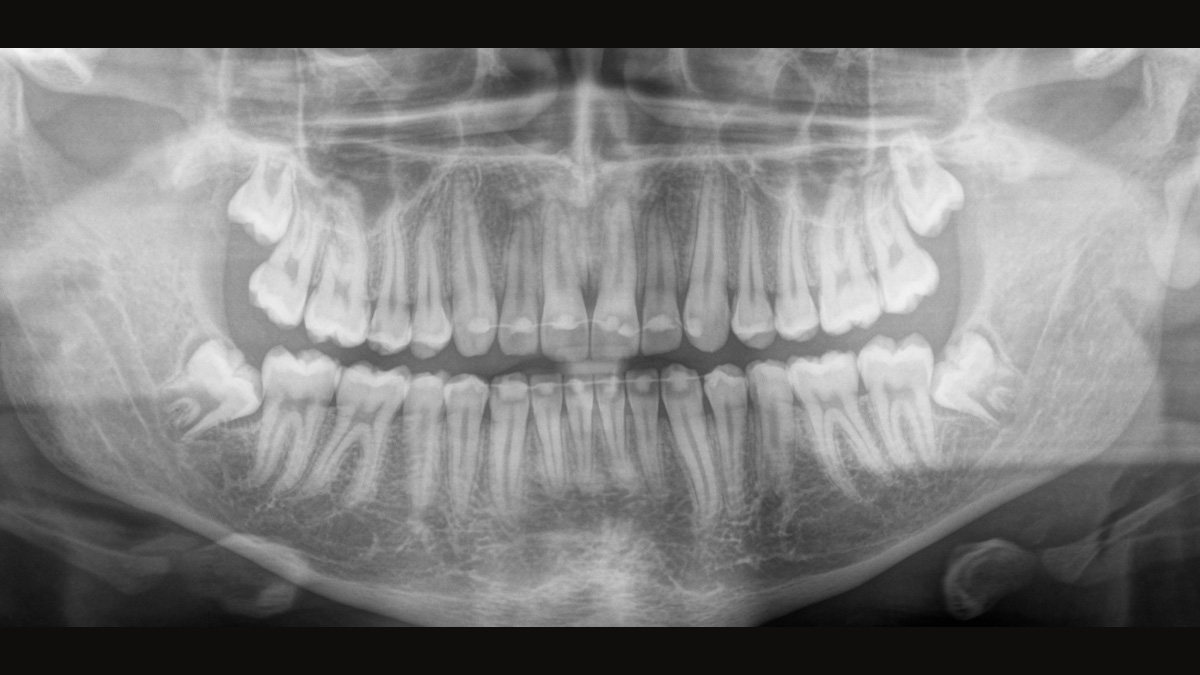

The Direct Conversion Sensor (DCS) has revolutionised the standard of panoramic imaging. X-rays are converted directly into electrical signals. Thus, there is no signal loss due to light conversion, as is the case with conventional systems. The result: images with a high level of sharpness and contrast – even at an extremely low radiation dose. For accurate diagnostic information to support targeted treatment.

The image below shows a panoramic X-ray without and with DCS technology. Using the arrow, drag the control across the image to see the difference the direct conversion sensor makes to the image quality and diagnostic possibilities.